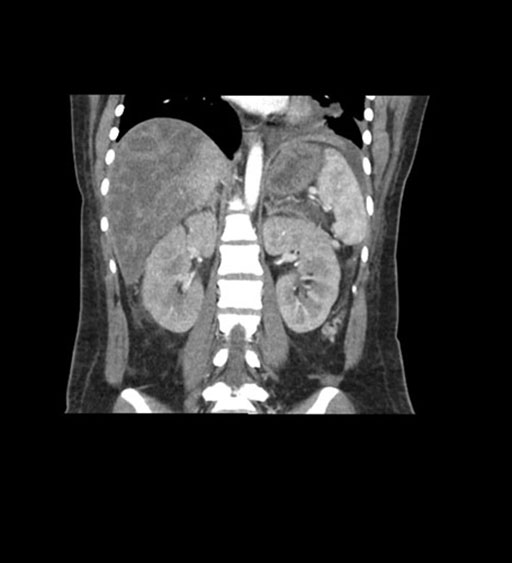

Coronal Arterial

Coronal Venous